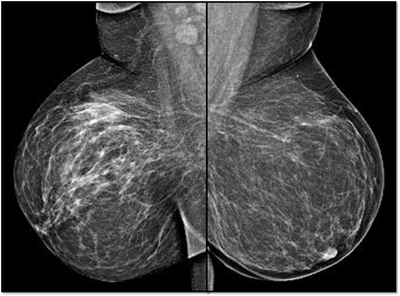

Carcinoma left breast(1975), treated and breast implantation done. Implant rupture (2012). Follow up mammogram in 2017, shows left axillary adenopathy.